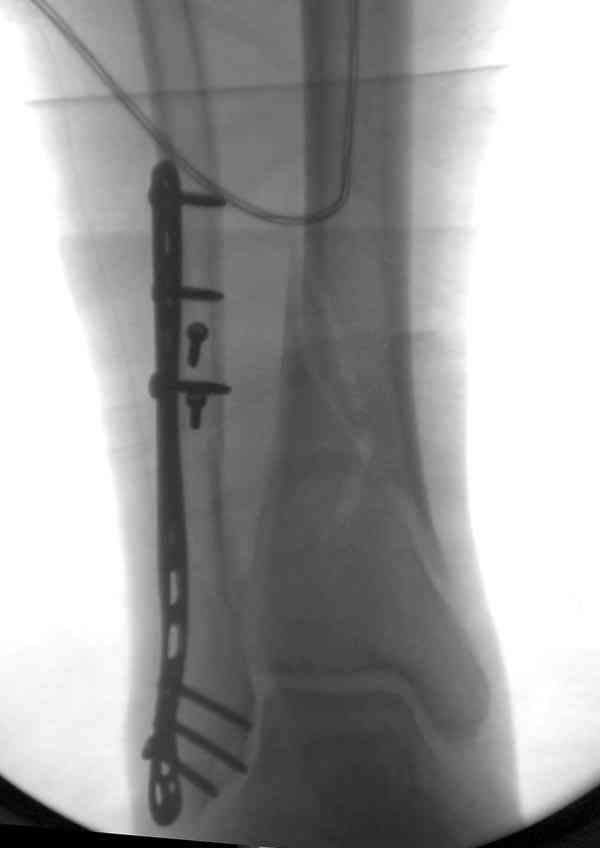

Удлинение малоберцовой можно техникой вставления в зону остеотомии расширителя или инструментом из набора АО articulate tension device. Толкателем за счет проведенного в проксимальной части пластины

дополнительного шурупа. Пару снимков из этапов фиксации: мортизный снимок, техника фиксации

лодыжки, копии из книги

Спасибо за совет,

тяжело будет решиться на повторную операцию, но скорее всего придется произвести поперечную остеотомию малоберцовой кости, создать дефект и произвести его пластику аутокостью или тутопластом, чтобы были способны выдержать раннюю нагрузку, фиксацию АО 1-3 трубчатой пластиной, перепровести 1-2 3,5 мм блокирующих винта. Если в сентябре пациентка даст согласие, выложу новые снимки.